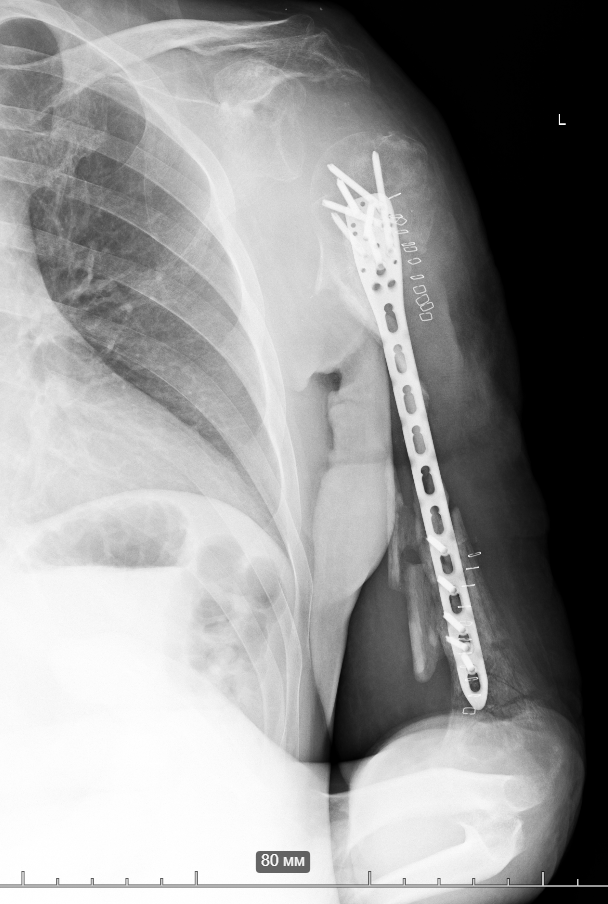

So, together with Vasyl Parii and Denys Dolgush, instead of performing massive bone grafting immediately, we decided to stabilize the severely damaged humerus (see X-rays) with a plate using a minimally invasive approach — and took new tissue samples for culture. In peacetime and in case of a normal civilian injury (usually the main bacteria in such cases is Staphylococcus Aureus), we would do bone grafting simultaneously with internal fixation. But the presence of the “Iraqi bacteria” in early investigations does not allow this; the risk of severe complications is too high.

If the cultures come back sterile, we’ll proceed with the grafting.

If not, we’ll continue with aggressive antibiotic therapy.

Then, surgery on the brachial plexus will be necessary (there is a nerve injury).

If all goes well, we will work with the patient to determine what to do about the shoulder joint.

Most likely, it will need to be fused (arthrodesis surgical procedure) — the deltoid muscle and parts of the rotator cuff are missing, and we still don’t know the full extent of nerve recovery (although there’s some positive progress).

We’ll see.